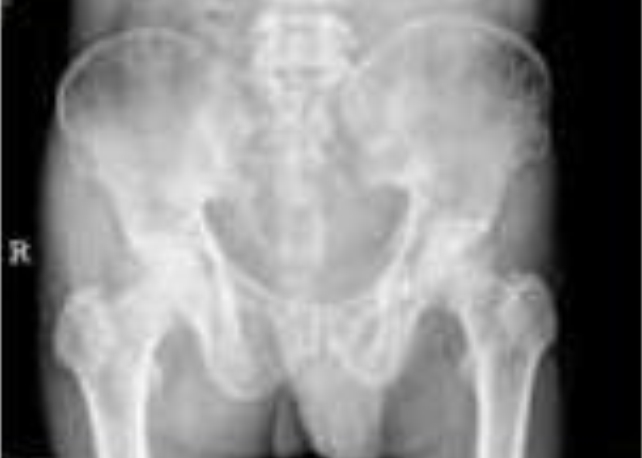

广泛骨质疏松,满布大小不等穿凿样改变,髂骨翼有片状骨缺损。

x线诊断:多发骨髓瘤(multiple myeloma)

评论:此病起源于骨髓的浆细胞,异常增生的恶性肿瘤,无法根治。

年龄多偏高,好发于扁骨。早期发于颅骨者应与蛛网膜颗粒压迹鉴别。